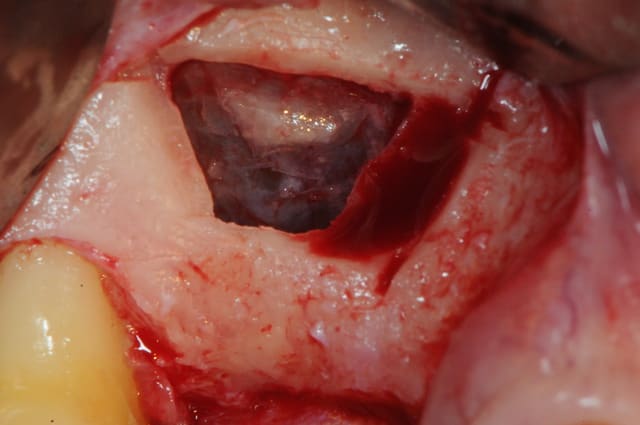

en attendant voici un des deux sinus de ce matin.

MP3 ( chez Pred) en comblement et ROG avec membrane et pins pour palier la forte concavité vestibulaire.

ps: je mets ces photos surtout parce que c'est rigolo de demander au patient de faire bouger sa membrane sinusienne...